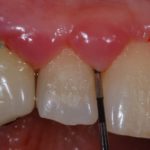

Alimentazione in caso di chirurgia parodontale, orale ed implantare

È comunque fuori di dubbio che, a seguito di chirurgia orale, parodontale ed implantare, siano da preferirsi i cibi altamente assimilabili e teneri, dal momento che il bisturi ha lasciato un segno importante e che la presenza di suture amplifica il disagio ed il senso di impotenza masticatoria.